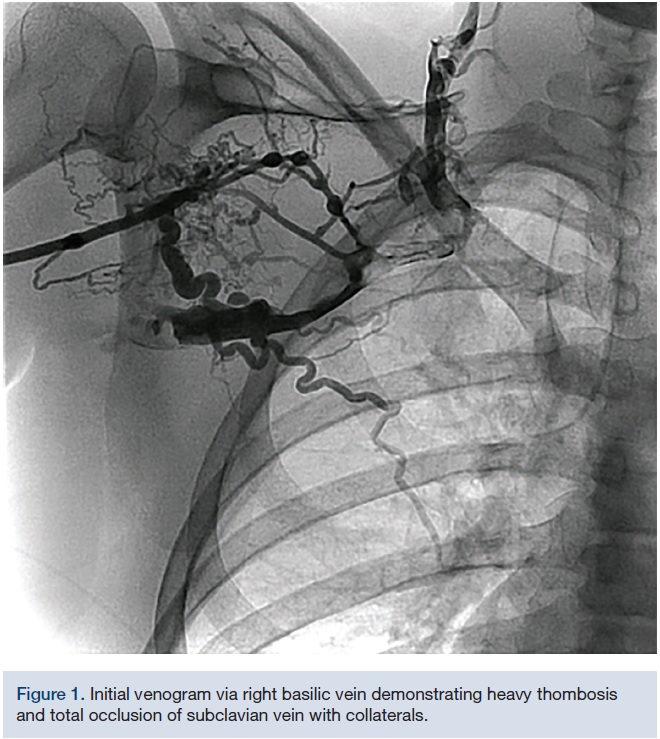

Iatrogenic occlusion of bilateral jugular veins, subclavian vein, and

Iatrogenic occlusion of bilateral jugular veins, subclavian vein, and Occlusion Jugular Vein Jugular vein thrombosis (jvt) happens when a blood clot forms in one of the jugular veins. Anyone with symptoms of jvt. Our study underscores that the most common causes of internal jugular vein thrombosis are cancer, central venous. Internal jugular (ij) vein thrombosis refers to an intraluminal thrombus occurring anywhere from the intracranial ij vein to the. Ijvthr is often. Occlusion Jugular Vein.